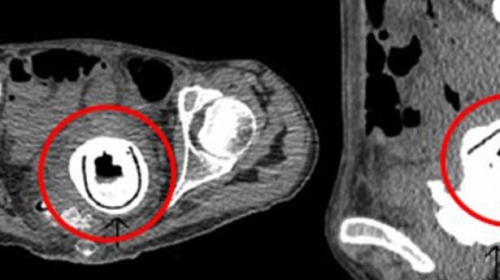

Žena čiji identitet nije otkriven javila se ljekaru jer je bila konstantno umorna. Nakon rendgenskog snimka, doktori su se začudili kada su u vagini 38-godišnje pacijentkinje vidjeli nešto veoma neobično.

U polnom organu je bila zaglavljena seksi igračka dugačka 13 centimetara.

Sve ovo ne bi bilo neobično da se žena javila ginekologu na vrijeme, ali zaboravila je na ovaj predmet koji se u njenom organizmu nalazi preko deset godina.

Ona je rekla da je igračku koristila jedne pijane noći sa svojim momkom, ali da se ne sjeća da je izvadila. Nakon što su hirurzi izvadili predmet, žena se potpuno oporavila.